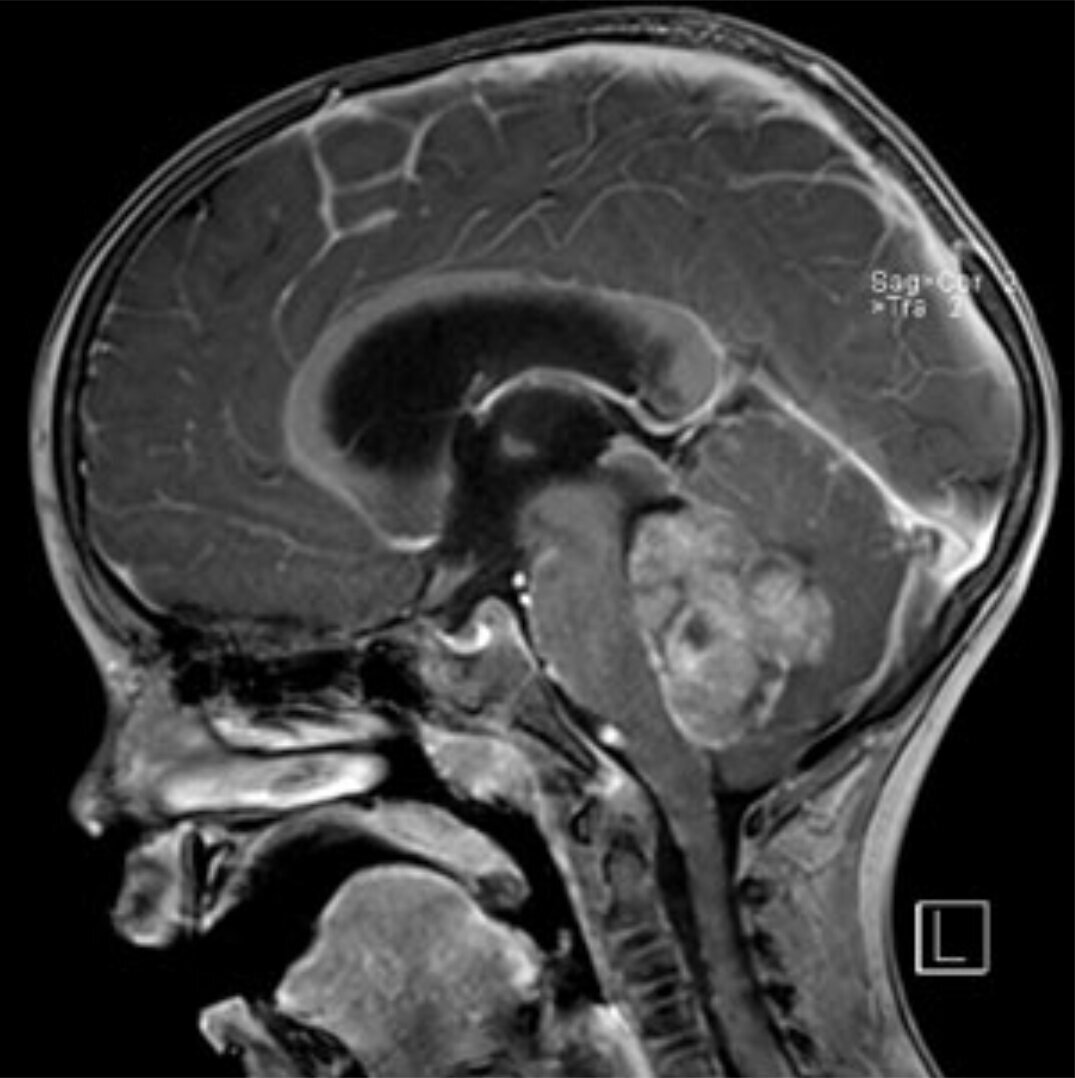

Pilozytische Astrozytome sind insgesamt die häufigsten Hirntumore im Kindesalter. Diese hirneigenen Tumoren kommen nahezu ausschließlich bei Kindern und jungen Erwachsenen vor. Sie können sowohl im Klein- als auch im Großhirn entstehen. Dank ihrer gutartigen Natur besteht hier die Möglichkeit, eine Heilung durch komplette chirurgische Resektion zu erzielen. Eine Nachbehandlung ist dann auch nicht erforderlich. Sollte die Tumorentfernung nur inkomplett möglich sein, wird bei erneutem Tumorwachstum neben der erneuten Resektion auch eine Bestrahlung oder Chemotherapie diskutiert.

Das Medulloblastom ist der häufigste bösartige ZNS-Tumor bei Kindern. Typischerweise entwickelt er sich in der hinteren Schädelgrube – meist im IV. Ventrikel – und wächst sowohl schnell als auch infiltrierend gegen das Kleinhirngewebe. Sogenannte Abtropfmetastasen entlang der Hirnwasserwege (Liquorräume) sind möglich. Die Behandlung besteht in der möglichst kompletten chirurgischen Entfernung, gefolgt von einer adjuvanten Therapie bestehend aus Chemotherapie und bei Kindern ab ca. 4 Jahren zusätzlich Strahlentherapie. Die Behandlungsergebnisse zeigen in den letzten Jahren eine deutliche Verbesserung. Durch die beschriebene Kombinationstherapie werden heute 5-Jahresüberlebenswahrscheinlichkeiten von 70-80 % erreicht.